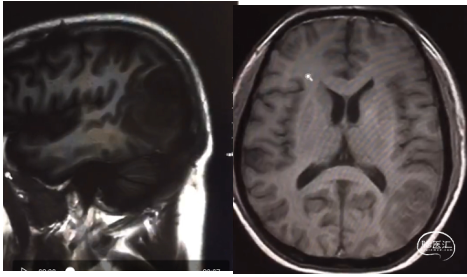

患者为中年男性,因“间断性头痛2月,加重1周”于2020年4月30日入院。入院时神经系统体征(-)。术前诊断为左顶枕叶胶质瘤。